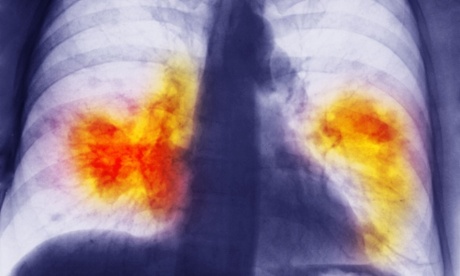

Chest x-ray showing lung cancer. In the 2000s, 18% of patients diagnosed with lung cancer in Austria survived – almost twice the rate in the UK.

She was only 50 but a lifetime of smoking had exacted a significant toll. Some months ago she was diagnosed with advanced lung cancer when a suspected infection failed to resolve. She said at the time that her main feeling was anger because nobody in her smoking group had ever been sick. She was determined to fight the cancer but her breathlessness worried me from the start. She couldn’t walk down a flat corridor without gulping for air. Correcting her anaemia and draining two litres of fluid from her lung helped her attain her goal of starting chemotherapy. Would the chemotherapy save her, a daughter had asked. It might help improve quality of life, I had answered honestly, but given her condition I wasn’t optimistic about extending survival.